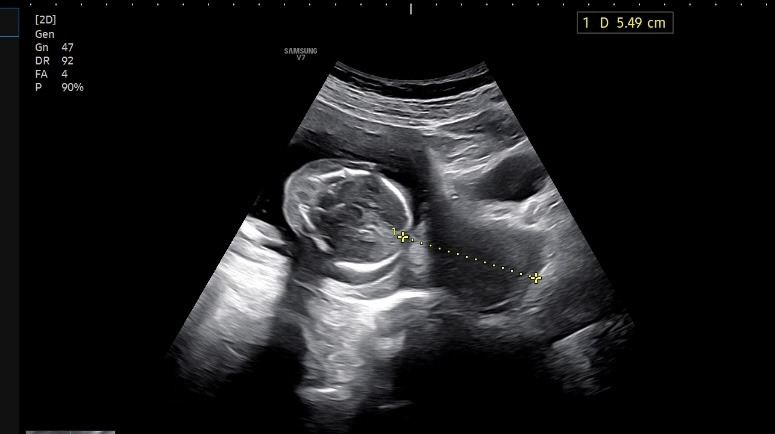

자궁 경부 길이도 좋고 주수에 맞게 건강히 잘 크고 있답니다.